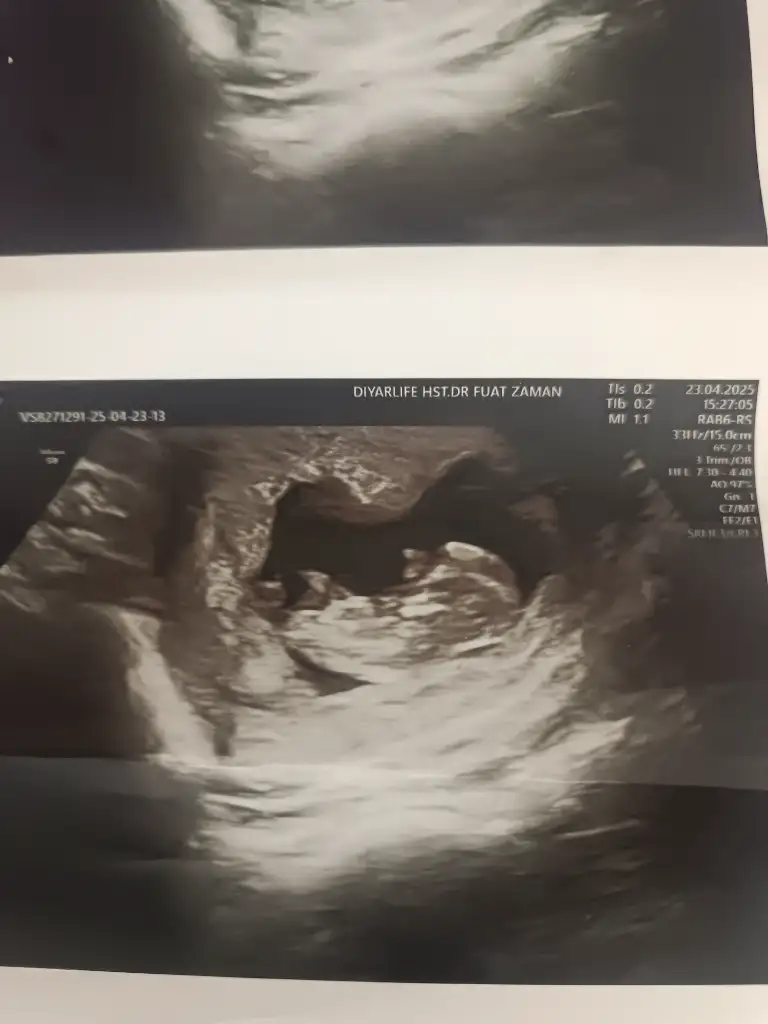

Banada bakar mısınız 12 haftalık

Eklentiler

• 772a7cb7-dd46-4148-b878-492734ef6f59.webp

39,1 KB · Görüntüleme: 50

• 0ae49c84-b353-4504-ba74-de5b3a1e9d6a.webp

48,1 KB · Görüntüleme: 51